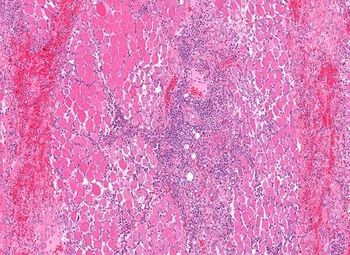

For a woman of her age and medical history with a weight problem, early osteoarthritis might not be an unreasonable diagnosis for knee pain and swelling after treadmill walking. But in rheumatology, things are so often not what they seem at first glance. What is your diagnosis?